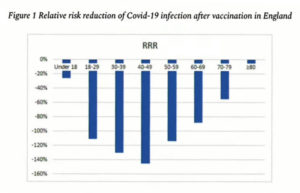

Data out of England corroborates this effect. A negative relative risk reduction for Covid infection after vaccination is most pronounced in the 40-49 year-old range, at minus (-) 140%. But every age group is in the negative.